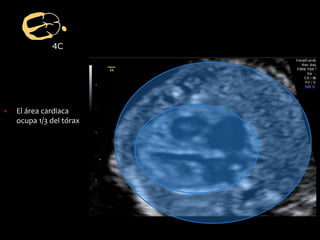

▪ El área cardiaca

ocupa 1/3 del tórax